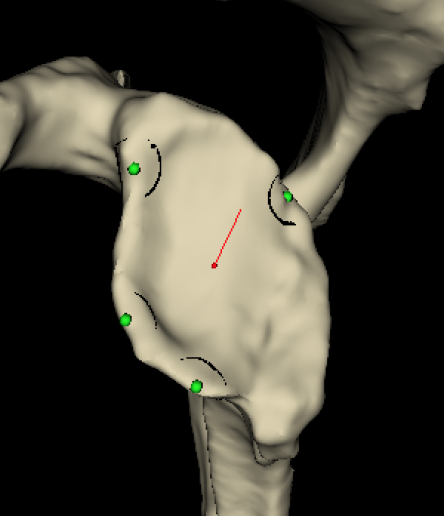

2. 3D CT templating

- templates glenoid component

- creates guide that matches glenoid

- allows placement of guide pin

Insert guide pin